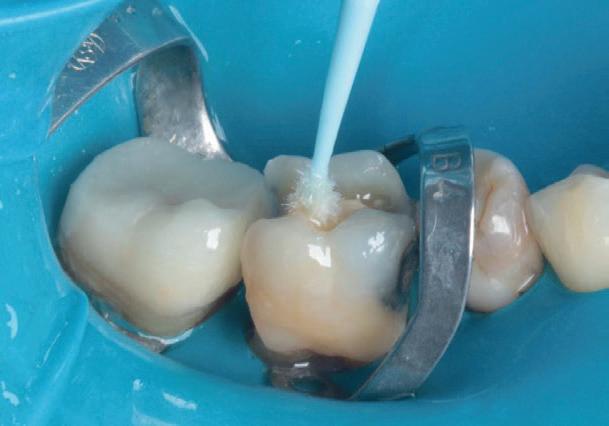

Materialul Biodentine™ a fost parțial îndepărtat și peste acesta s-a plasat o obturație din compozit (fig. 11). S-a efectuat o gravare selectivă a smalțului, urmată de aplicarea unui sistem adeziv (Palfique Bond®, Tokuyama) (fig. 12-13). După foto-

polimerizare, s-a fixat sistemul de matrice (SeptoMatrix, Septodont) și s-a utilizat o matrice mare cu un inel moale pentru un contur mai bun și un punct de contact proximal (fig. 14). Restaurarea a fost începută în porțiunea distală, transformând cavitatea de clasa a II-a într-o cavitate de clasa I (fig. 15). În final, suprafața ocluzală a fost restaurată folosind compozitul Palfique LX5® (Tokuyama) (fig. 16). După fotopolimerizare, s-a aplicat gel de glicerină pentru a permite o mai bună fotoactivare a stratului superficial. Restaurarea a fost apoi finisată și lustruită, înainte de îndepărtarea digii de cauciuc și verificarea ocluziei (fig. 17).

Figurile:

6. Biodentine™ aplicat prin procedura

Bio Bulk-Fill. 7. Situația clinică după 12 minute și îndepărtarea matricii.

8. Situația clinică după îndepărtarea digii de cauciuc. 9. Radiografia de control la 2 luni postoperator.

14. Plasarea unui sistem de matrice (Septomatrix, Septodont)

15. Reconstrucția cu compozit a peretelui distal.

16. Restaurarea imediat după finalizare.